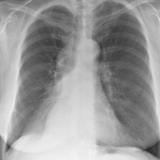

RLL collapse 4 PA

Date: 03/02/2006

Views: 3251